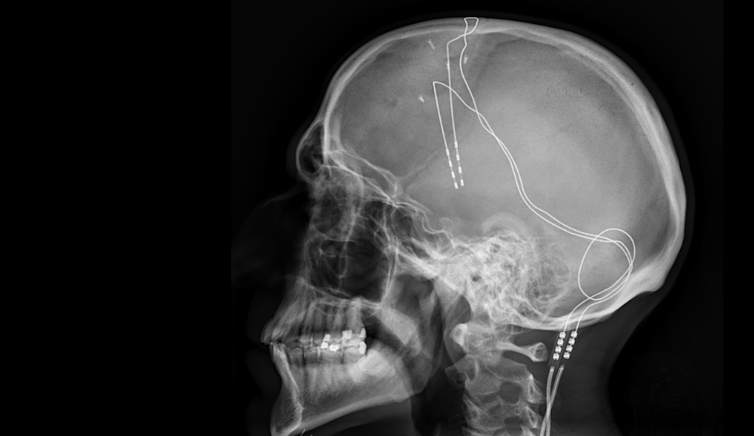

In deep brain stimulation, electrodes – the pale white lines – are implanted into a patient’s brain and connected to a battery in a person’s chest. Jmarchn/Wikimedia Commons, CC BY-SA

“Deep brain stimulation involves the implantation of electrodes in the deeper areas of the brain,” Davis explains. These electrodes then transfer into the brain itself small electrical currents that a doctor and their patient try to tune correctly. As Davis explains, “Basically we’re looking to find the settings where the patient feels that their mood is better, their anxiety is less and they have more energy.”